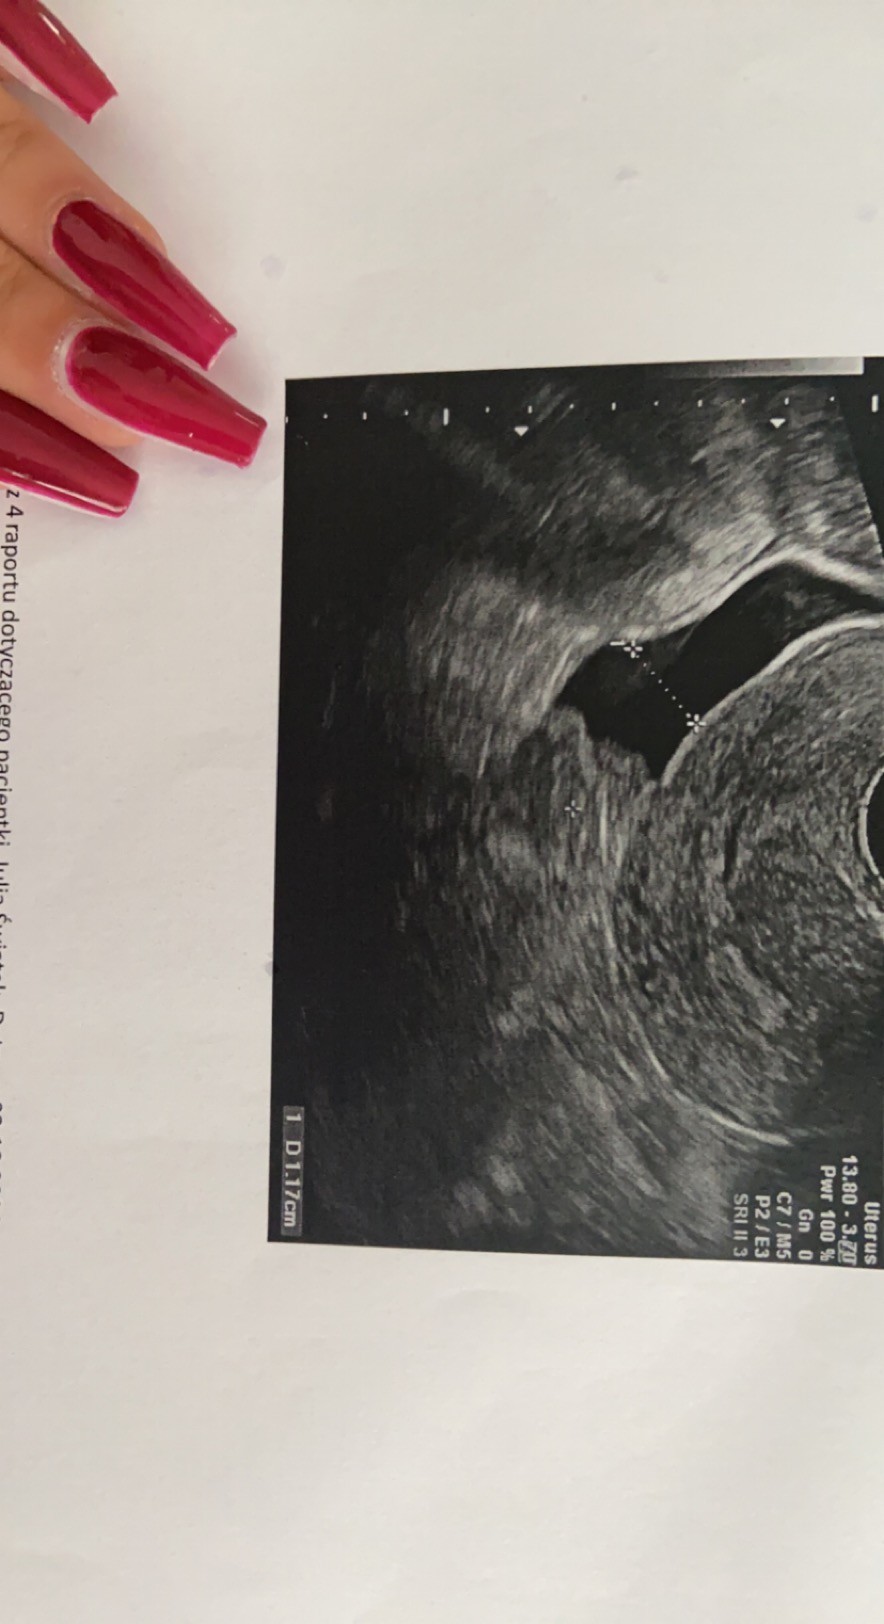

Płyn za macica

Czesc kochane. Niedawno byłam u ginekologa, ale zbyt wiele mi nie powiedział. Jest płyn za macica (zdjęcie), ale stwierdził, że to może być infekcja albo owulacja albo w ogóle wszystko. Endo 8mm. Sam ginekolog stwierdził, że może była owulacja, może nie, śluz taki jak po owulacji. Także mam pytanko do dziewuszek z monitoringiem, wasz gin zaobserowal płyn za macica? Bo mam tak 1 raz a u ginekologa jestem co chwile.

• D48BD832-2B8B-4A63-8542-59C6EAE4493C.jpeg